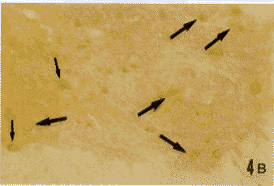

图4A 颈段脊髓腹角mGluR1和ER双重免疫组织化学染色切片。图4B为A的相邻连续切片,IL-2免疫组织化学染色。各种箭头和三角所指同图1 ×100

Fig.4 A mGluR1 and ER double immunohistochemical staining section of the ventral horn of cervical spinal cord.B:IL-2 immunohistochemical staining serial neighbor section of A.The targets pointed by different arrows and triangles are the same as in Fig.1. ×100讨 论

在大鼠大脑皮质、延髓和脊髓颈、胸、腰段均可见到mGluR1,ER和IL-2免疫反应性神经细胞。mGluR1免疫反应产物为蓝黑色,位于胞膜;ER免疫反应产物为棕褐色,位于胞浆或核内。IL-2免疫反应产物亦为棕褐色,位于胞浆内。在大脑皮质,上述3种阳性细胞分布于皮质各层,以第Ⅴ层最为密集。在数量上,mGluR1阳性细胞最多,ER阳性细胞次之,IL-2阳性细胞最少。阳性细胞以锥体形大、中细胞为主(图1A,B)。在延髓和脊髓,mGluR1和ER阳性神经元的分布已述于我们的另一篇文章[8],主要分布于迷走神经背核、孤束核、三叉神经脊束核和网状结构及脊髓的腹角、背角和中间带,以mGluR1阳性神经细胞占优势,以上细胞以中等大多角形细胞为主(图2A,3A,4A)。IL-2阳性细胞在延髓和脊髓的分布均较上述两种细胞少(图2B,3B,4B),但分布类型相似。本实验主要对大脑皮质、延髓网状结构和脊髓腹角的含上述免疫、神经、内分泌3类物质的细胞进行研究。在mGluR1和ER双重染色的切片上,可见3种细胞:(1)mGluR1单标细胞,胞膜为蓝黑色;(2)ER单标细胞,胞浆或胞核呈棕褐色;(3)mGluR1/ER双标细胞,胞膜为蓝黑色,胞浆和胞核为棕褐色。双标细胞约占全部(单+双)标记细胞的50%~60%(依部位而异,图1A,2A,3A,4A)。双标细胞的形态主要为锥体和多极细胞。通过对相邻两张切片的投影核对,证实在大鼠大脑皮质、延髓网状结构和脊髓腹角内存在mGluR1/ER/IL-2三重标记细胞,即同一神经细胞既为mGluR1/ER阳性,又呈IL-2阳性,1个细胞在相邻两张切片上的影像重迭(比较图1A与1B,图2A与2B,图3A与3B,图4A与4B)。三标细胞约占mGluR1/ER双标细胞总数的30%。